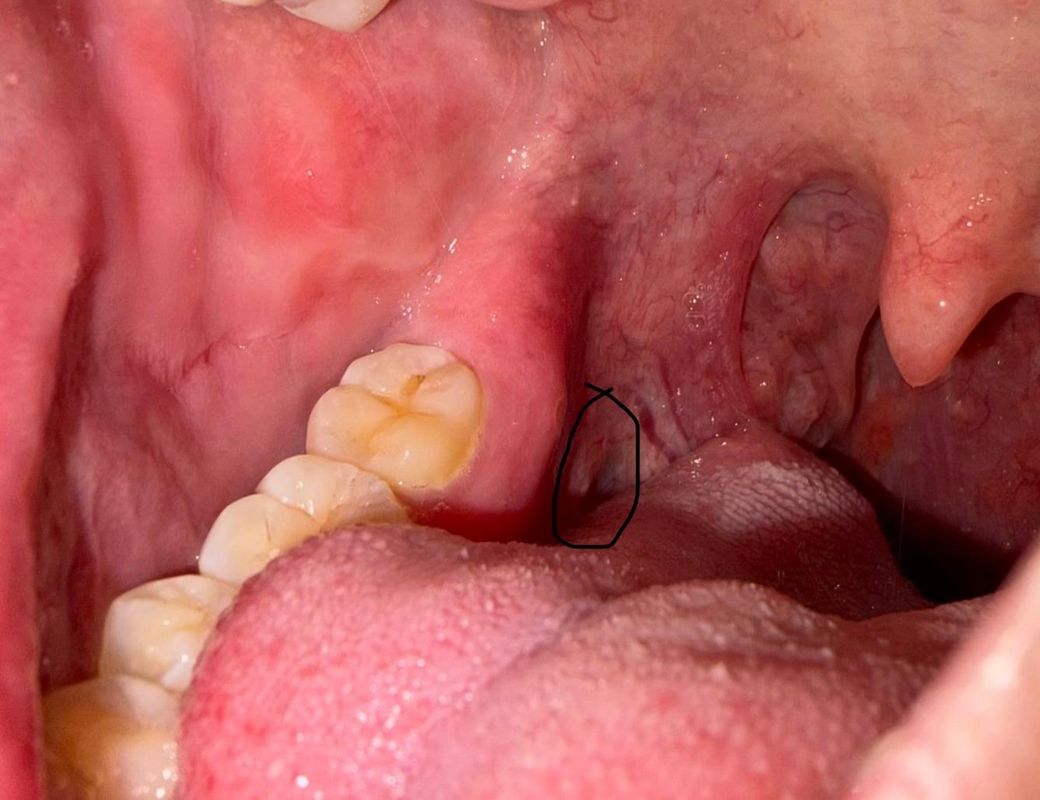

오른쪽 어금니 뒷 쪽과 혓바닥 뒷 부분 사이에 있는 옆 쪽의 잇몸이 이틀 전인가 부터 아프더라고요

워낙 뒤 쪽에 있고 안 쪽에 있어서 폰 후레쉬로 비춰도 자세히는 확인이 안되는 위치라 정확히는 저도 확인이 안되고요

• 2번 째 사진